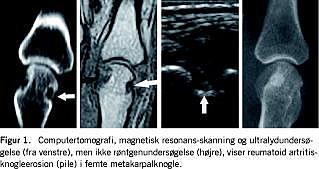

Magnetisk resonans (MR)-skanning og ultralydundersøgelse (UL) anvendes i stigende grad ved undersøgelser af inflammatoriske ledlidelser, og er begge velegnede til undersøgelse af børn. I en sammenligning med højopløsningscomputertomografi (Figur 1 ) er det nu bevist, at MR- og UL-påviste knogleerosioner ved RA, selv når de ikke ses med røntgenundersøgelse, repræsenterer et reelt tab af kortikal knogle, dvs. er sande erosioner [5].